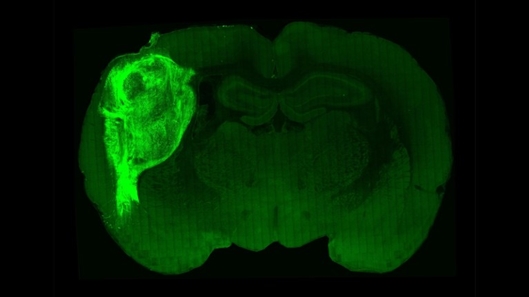

研究人员将人类大脑器官(亮绿色)移植到一只新生幼鼠的大脑中,创造出神经元界面的混合大脑。 图片来源:斯坦福大学

为了给类脑器官提供这种刺激和支持,美国斯坦福大学神经科学家Sergiu Pasca团队从人类干细胞中培养出这种结构,然后将它们注射到新生幼鼠的大脑中,期望人类细胞能和小鼠自己的细胞一起生长。研究小组将这些类器官放置在一个叫做体感大脑皮层的大脑区域,该区域从小鼠的胡须和其他感觉器官接收信号,然后将它们传递到大脑的其他区域来分析这些信号。